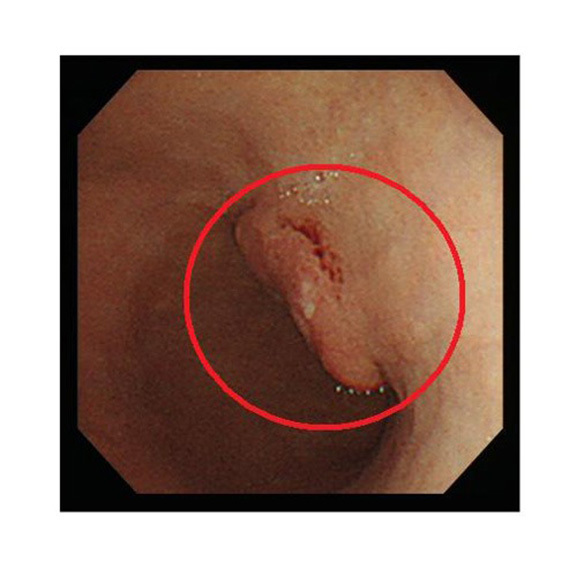

NBI:狭帯域光法システムで光を照らして観察します

NBI

食道・胃・大腸内の様子を明確に画像表示し、より癌を見つけやすくなりました。